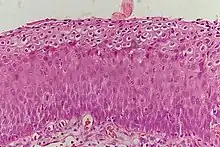

Normal cervical epithelium

Historically, abnormal changes of cervical epithelial cells were described as mild, moderate, or severe epithelial dysplasia. In 1988 the National Cancer Institute developed "The Bethesda System for Reporting Cervical/Vaginal Cytologic Diagnoses".[12] This system provides a uniform way to describe abnormal epithelial cells and determine specimen quality, thus providing clear guidance for clinical management. These abnormalities were classified as squamous or glandular and then further classified by the stage of dysplasia: atypical cells, mild, moderate, severe, and carcinoma.[13]

Depending on several factors and the location of the lesion, CIN can start in any of the three stages and can either progress or regress.[1] The grade of squamous intraepithelial lesion can vary.

CIN is classified in grades:[14]

Histology Grade Corresponding Cytology Description Image

CIN 1 (Grade I) Low-grade squamous intraepithelial lesion (LSIL)

• Mild epithelial dysplasia

• Confined to the basal 1/3 of the epithelium

• Typically corresponds to infection with HPV

• High rate of regression back to normal cells

• Usually managed expectantly